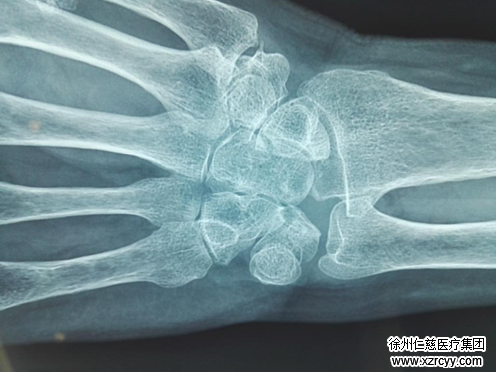

接诊后,betway在线登陆手外科陈步国仔细为王女士做了检查。检查发现其左手肿胀及疼痛、腕关节活动受限、被动过伸中指的掌指关节也可引起腕部疼痛。与“月骨无菌性坏死”的几种症状十分符合,于是,陈主任建议王女士去做一个X线照片。

X线照片印证了陈主任的判断。导致王女士手腕疼痛的罪魁祸首被“抓”了出来——左腕月骨无菌性坏死。

3、早期X线照片可无表现,一般在几个月后才出现X线改变。X线片可见月骨致密、变窄,而周围的腕骨则疏松,几年后月骨外形变为不规则。